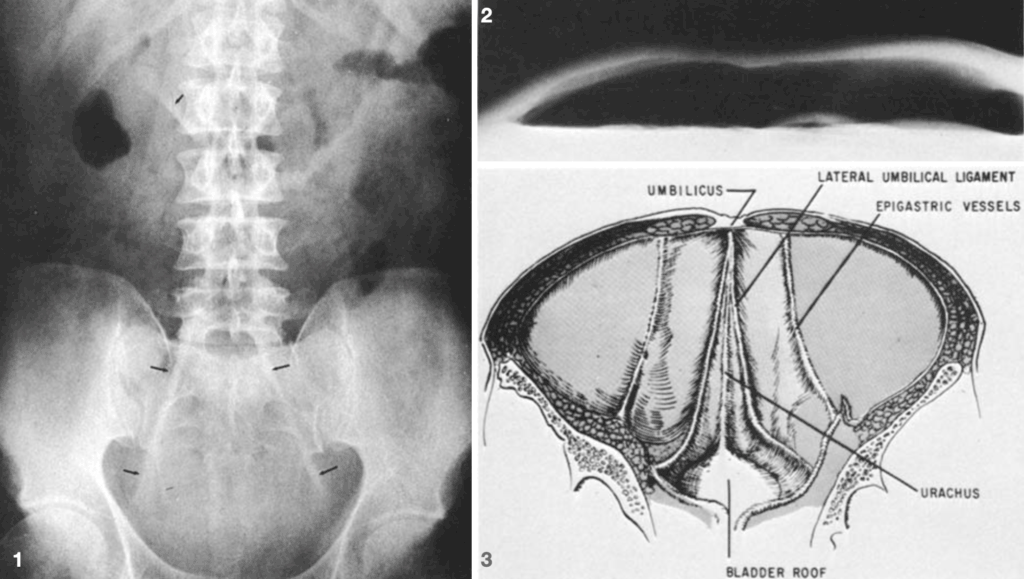

1973 – Charles I. Weiner et al presented three cases demonstrating a further sign of pneumoperitoneum – the inverted V sign. Free air outlining the lateral umbilical ligaments makes these structures visible in the lower abdomen, forming an “inverted V” as they course inferiorly and laterally from the umbilicus. The ligaments contain the umbilical arterial remnants and may be unilaterally or fractionally visualized.

Fig. 1. Supine AXR showing lateral umbilical ligaments (lower arrows) diverging from the umbilicus. Free air also made the falciform ligament visible (upper arrow).

Fig. 2. Cross-table lateral AXR demonstrating massive pneumoperitoneum.

Fig. 3. Illustration of inner surface of lower anterior abdominal wall. Weiner 1973